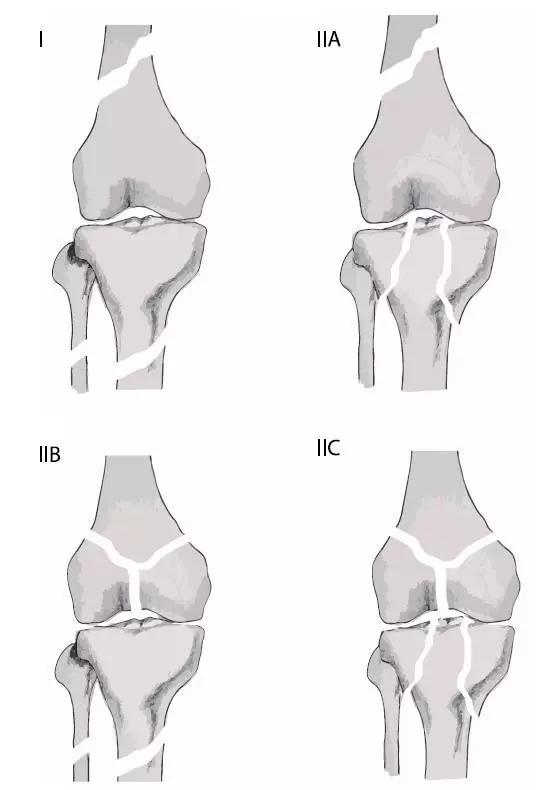

6. Pipkin 骨折

股骨头骨折。1957 年,Pipkin G 在文献中对其进行详细的描述并分型,至今仍在很多文献中被采用。

-

Ⅰ型:骨折块在圆韧带的下方;

Ⅱ型:骨折块在圆韧带的上方;

Ⅲ型:Ⅰ、Ⅱ两型任意一种伴股骨颈骨折;

Ⅳ型:Ⅰ、Ⅱ两型任意一种伴髋臼骨折 。